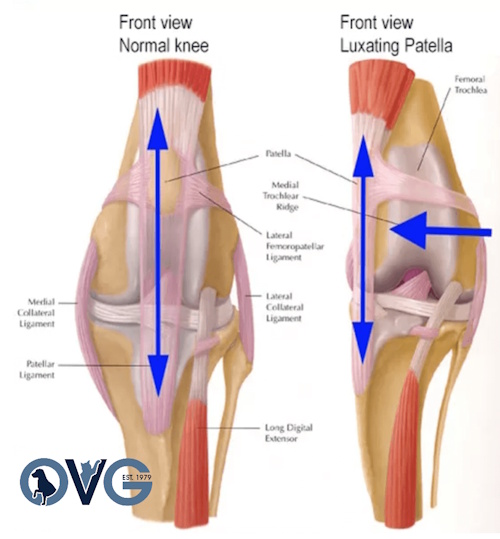

Patellar Luxation

Diagram of a Patella Luxation

Surgical Treatments for Patellar Luxation

- Tibial Tuberosity Transposition

- Femoral Varus Osteotomy

- Recession Sulcoplasty

- Soft Tissue Reconstruction